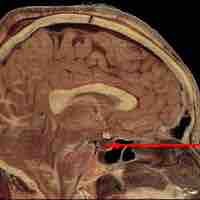

The pituitary gland is connected to the hypothalamus and secretes nine hormones that regulate body homeostasis.

The pituitary gland consists of the anterior pituitary and the posterior pituitary.